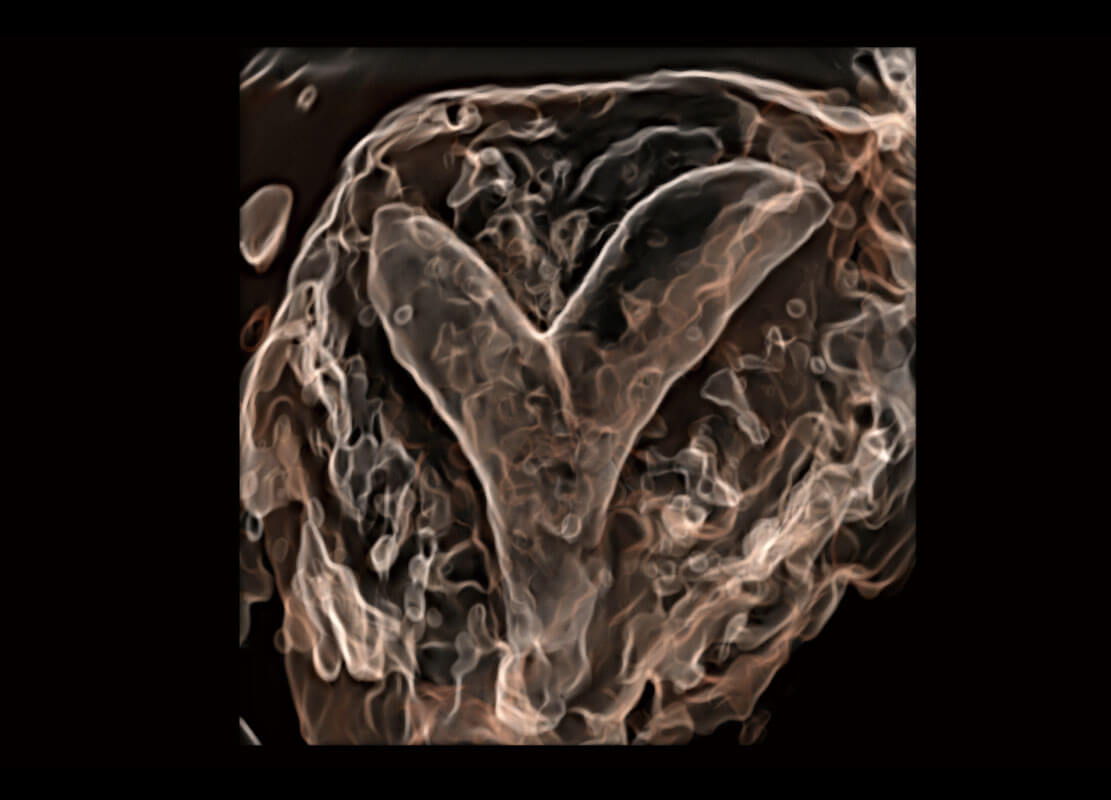

右室双出口

胎心容积成像